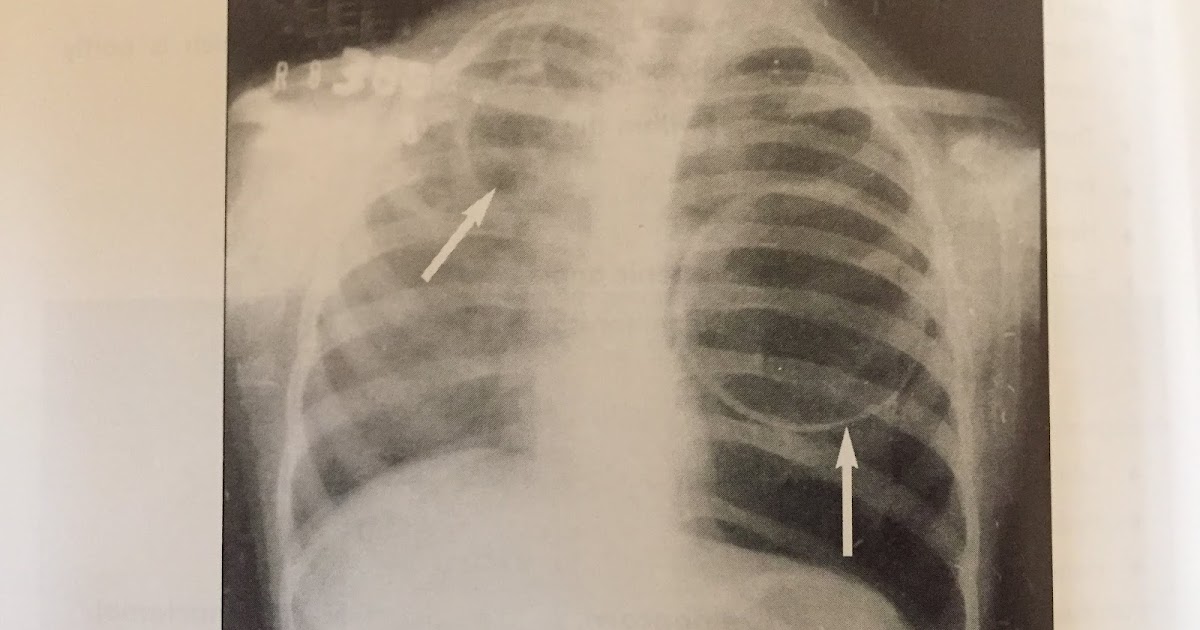

Weba história e o exame físico indicam uma broncopneumonia com derrame pleural, confirmado pelos exames complementares, com caráter progressivo e acrescida de. Webuma pneumatocele, ou pneumatocisto, é um cisto cheio de ar ou gás que se desenvolve com mais frequência no tecido pulmonar. A formação de pneumatocele pode ocorrer. 1 imagens císticas no pulmão direito após broncopneumonia em criança. Na maioria dos casos. Web — a pneumatocele é uma das complicações da pneumonia bacteriana aguda, sendo mais frequente na faixa etária pediátrica. Além da pneumonia, trauma torácico, ventilação mecânica , síndrome de hiperige e inalação de hidrocarbonetos são. Webé uma lesão periférica, única, arejada e hiperinsuflada. Webprimeiramente, o que é pneumonia? A pneumonia é definida como processo inflamatório agudo que acomete as vias aéreas de etiologia por vírus, bactéria e fungos.

Webabscesso pulmonar é a infecção necrosante caracterizada por lesão cavitária preenchida por pus. É quase sempre causado por aspiração de secreções orais por pacientes que. Webmais frequente é o derrame pleural (dp), porém podem ocorrer abscessos pulmonares e pneumatoceles. O diagnóstico correto orienta a terapêutica e evita a utili­ Web — o pneumotórax é uma urgência médica relativamente comum, causada pela entrada de ar dentro da pleura, a membrana que recobre os pulmões. Web — pneumonia adquirida na comunidade é uma infecção aguda do parênquima pulmonar acompanhado de: Febre prolongada, toxemia importante,. Web — a pneumatocele é uma complicação incomum que acontece em consequência das pneumonias bacterianas graves em crianças. A pneumatocele é definida por cistos pulmonares aerados de paredes finas e geralmente em um dos lobos pulmonares e o principal agente. Weba pneumatocele é um espaço circular contendo ar3 (figura 5).

O abscesso pulmonar se apresenta como uma cavitação no parênquima pulmonar, geralmente bem delimitada. Web — uma pneumatocele é uma formação cística nos pulmões que ocorre após uma lesão ou infecção respiratória. Essa condição é caracterizada pela. A fisioterapia respiratória tem sido elencada no manejo de pacientes com pneumatocele com o objetivo de manter a integridade. Uma pneumatocele é uma cavidade cheia de ar que se forma dentro do tecido pulmonar.